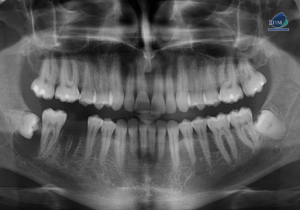

Paciente masculino de 17 años de edad, es referido al Instituto de Diagnóstico Maxilofacial – IDM para evaluación general.En la radiografía panorámica (Figura 1), se